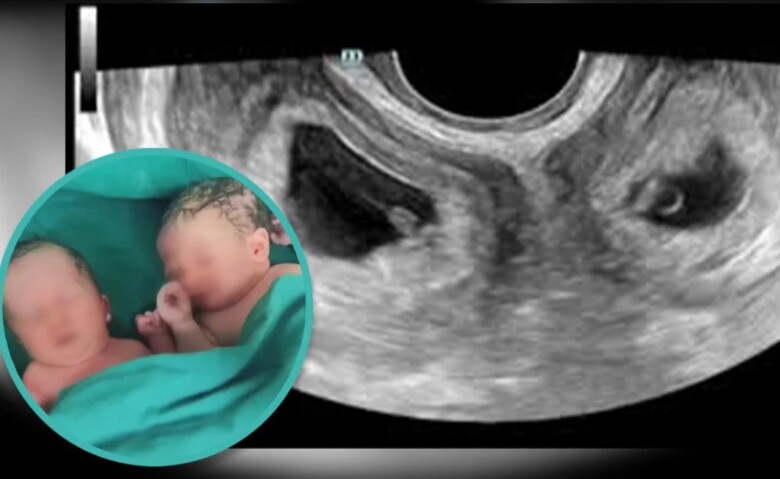

Tờ SCMP đưa tin, một người phụ nữ ở tây bắc Trung Quốc khi chào đời đã mắc chứng bệnh hiếm gặp khi có tới 2 tử cung. Vào tháng 9 vừa qua, cô đã thu hút sự chú ý khi chào đón cặp sinh đôi từ cả hai tử cung.

Tình trạng sở hữu buồng trứng đôi rất hiếm gặp nhưng phụ nữ sinh con thành công ở cả 2 tử cung lại còn hiếm gặp hơn. Cô Li đã sinh được một bé trai và một bé gái vào đầu tháng 9 tại Bệnh viện số 4 Tây An, tỉnh Thiểm Tây khi cô đang mang thai được tám tháng rưỡi.

Hai em bé chào đời khỏe mạnh, bé trai nặng 3,3kg và bé gái nặng 2,4kg. Người phụ nữ cùng cặp song sinh đã được xuất viện 4 ngày sau khi sinh, cả 3 mẹ con đều trong tình trạng rất tốt.

Cô Li đã sinh con thành công từ 2 tử cung riêng biệt.